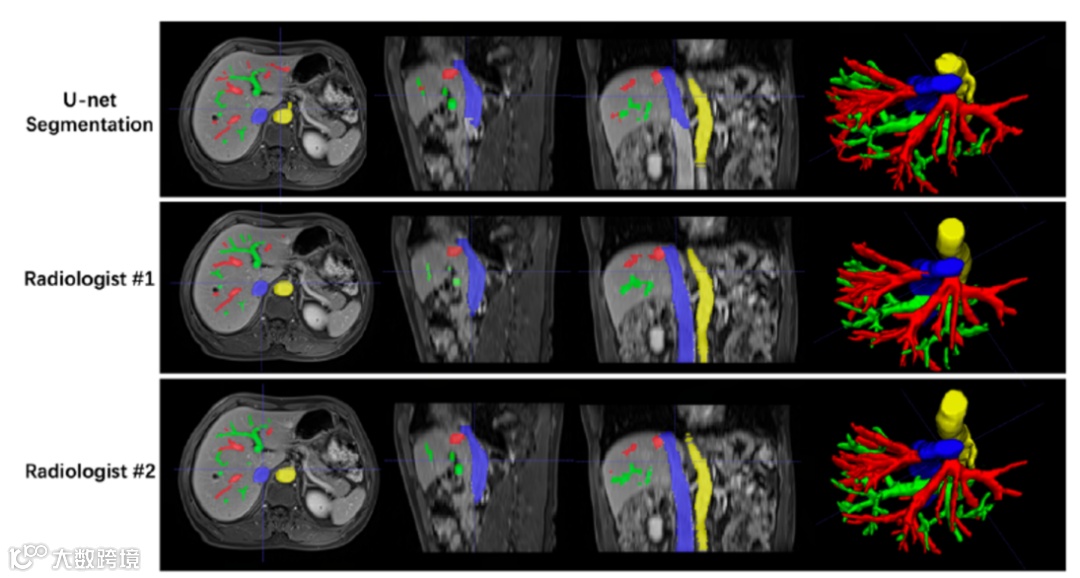

图1. 肝血管几何模型用于检测CSPH

(引自讲者幻灯)